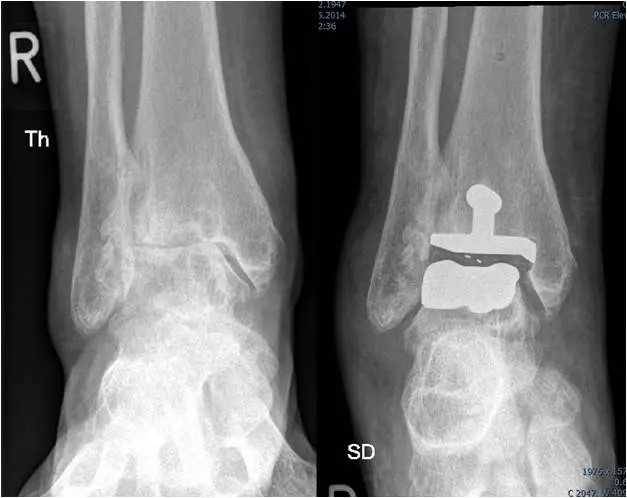

Das Röntgenbild des Sprunggelenkes in zwei Ebenen im Stand zeigt in fortgeschrittenen Fällen typische Arthrosezeichen:

• Gelenkspaltverschmälerung

• subchondrale Sklerosierung

• Exophyten

• Deformierung des Gelenkes

Röntgenbild einer OSG Arthrose mit starker Verschmälerung des Gelenkspalts

welche stadienabhängig unterschiedlich stark ausgeprägt sind.

OSG-Arthrose (rechts) behandelt mit einer OSG Prothese